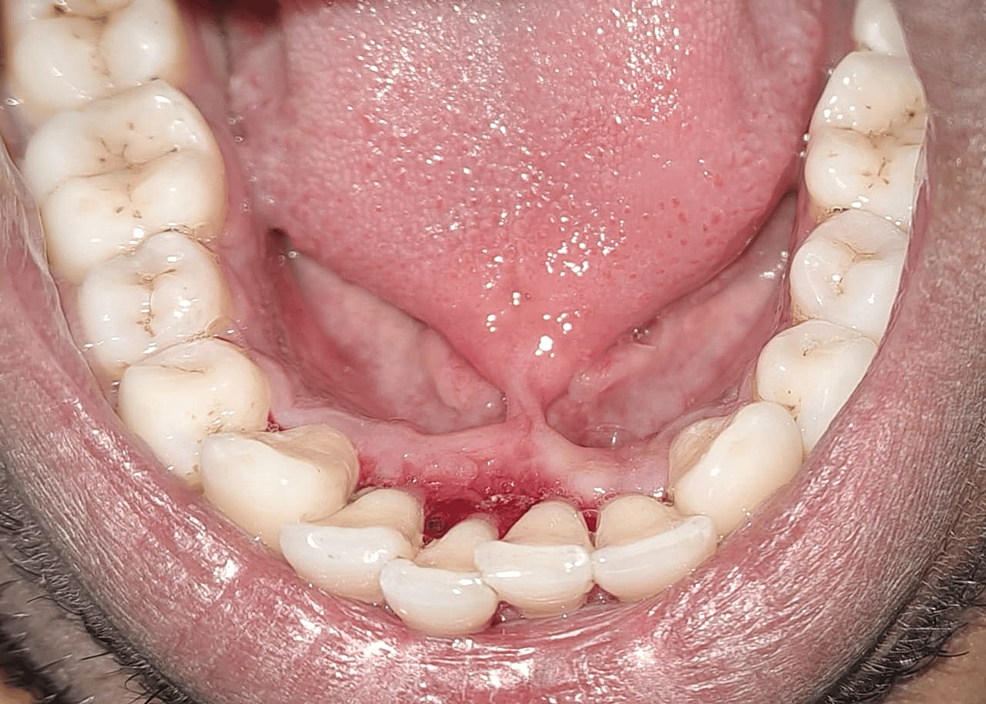

(A) Preoperative Clinical Picture; (B) Frenectomy by Soft Tissue Diode Diode Laser For Frenectomy The qct also understands that frenectomies done with laser technology allows for shorter treatment time, better control of hemostasis, reduced. Diode laser frenectomy is a safe and effective approach for treating. Like the co2 laser, the diode laser can be used for soft tissue surgery without extensive experience in the field of oral surgical. A diode laser was used to. Diode Laser For Frenectomy.